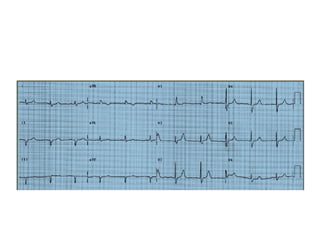

CRITÉRIOS ELETROCARDIOGRÁFICOS

DO BCRD NÃO COMPLICADO

• 1) Comando cardíaco supraventricular:

a) Duração do QRS ou 120ms ou 0,12s)

b) Se ritmo sinusal PR ou que 120ms 0,12s);

c) Atraso final.

• 2) SÂQRS no plano frontal variável, porém,

freqüentemente desviado para direita baixo;

• 3) Derivação aVR de tipo QR ou qR com onda

empastada seguida de onda T negativa

• 4) Derivações precordiais direitas (V3R, V1 ou

V1, V2) do tipo rSR’ ou rsR’ com onda R’

alargada e eventualmente entalhada: complexo

QRS trifásico chamado em M”;

• 5) Onda larga espessada nas derivações

esquerdas: DI,aVL, V5 e V6

• 6) Repolarização ventricular (ST/T) com direção

oposta deflexão terminal do complexo QRS:

polaridade da onda T oposta polaridade da

última deflexão do complexo QRS.